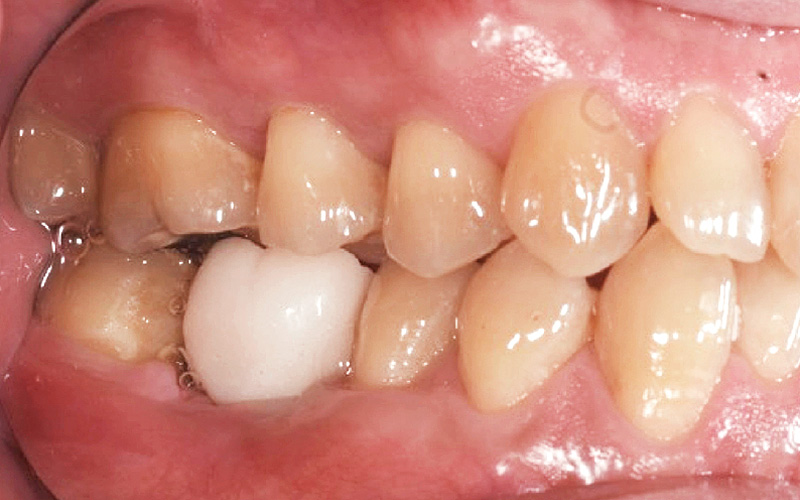

![[写真] 初診時の口腔内写真](/academic/dentalmagazine/wp-content/uploads/sites/2/2023/12/187-6_photo03.jpg)

図3 初診時の口腔内写真。 -

患者のパノラマX線所見では、欠損部における透過像は#47近心歯根面まで波及していることが確認された(図2)。歯周病学的口腔内所見(図3)ではPCR70%であり、広域性のステージⅠグレードBの歯周炎であったことから、GBR前の歯周基本治療を徹底し、患者の口腔内環境の向上・モチベーションの向上をそれぞれ図った。